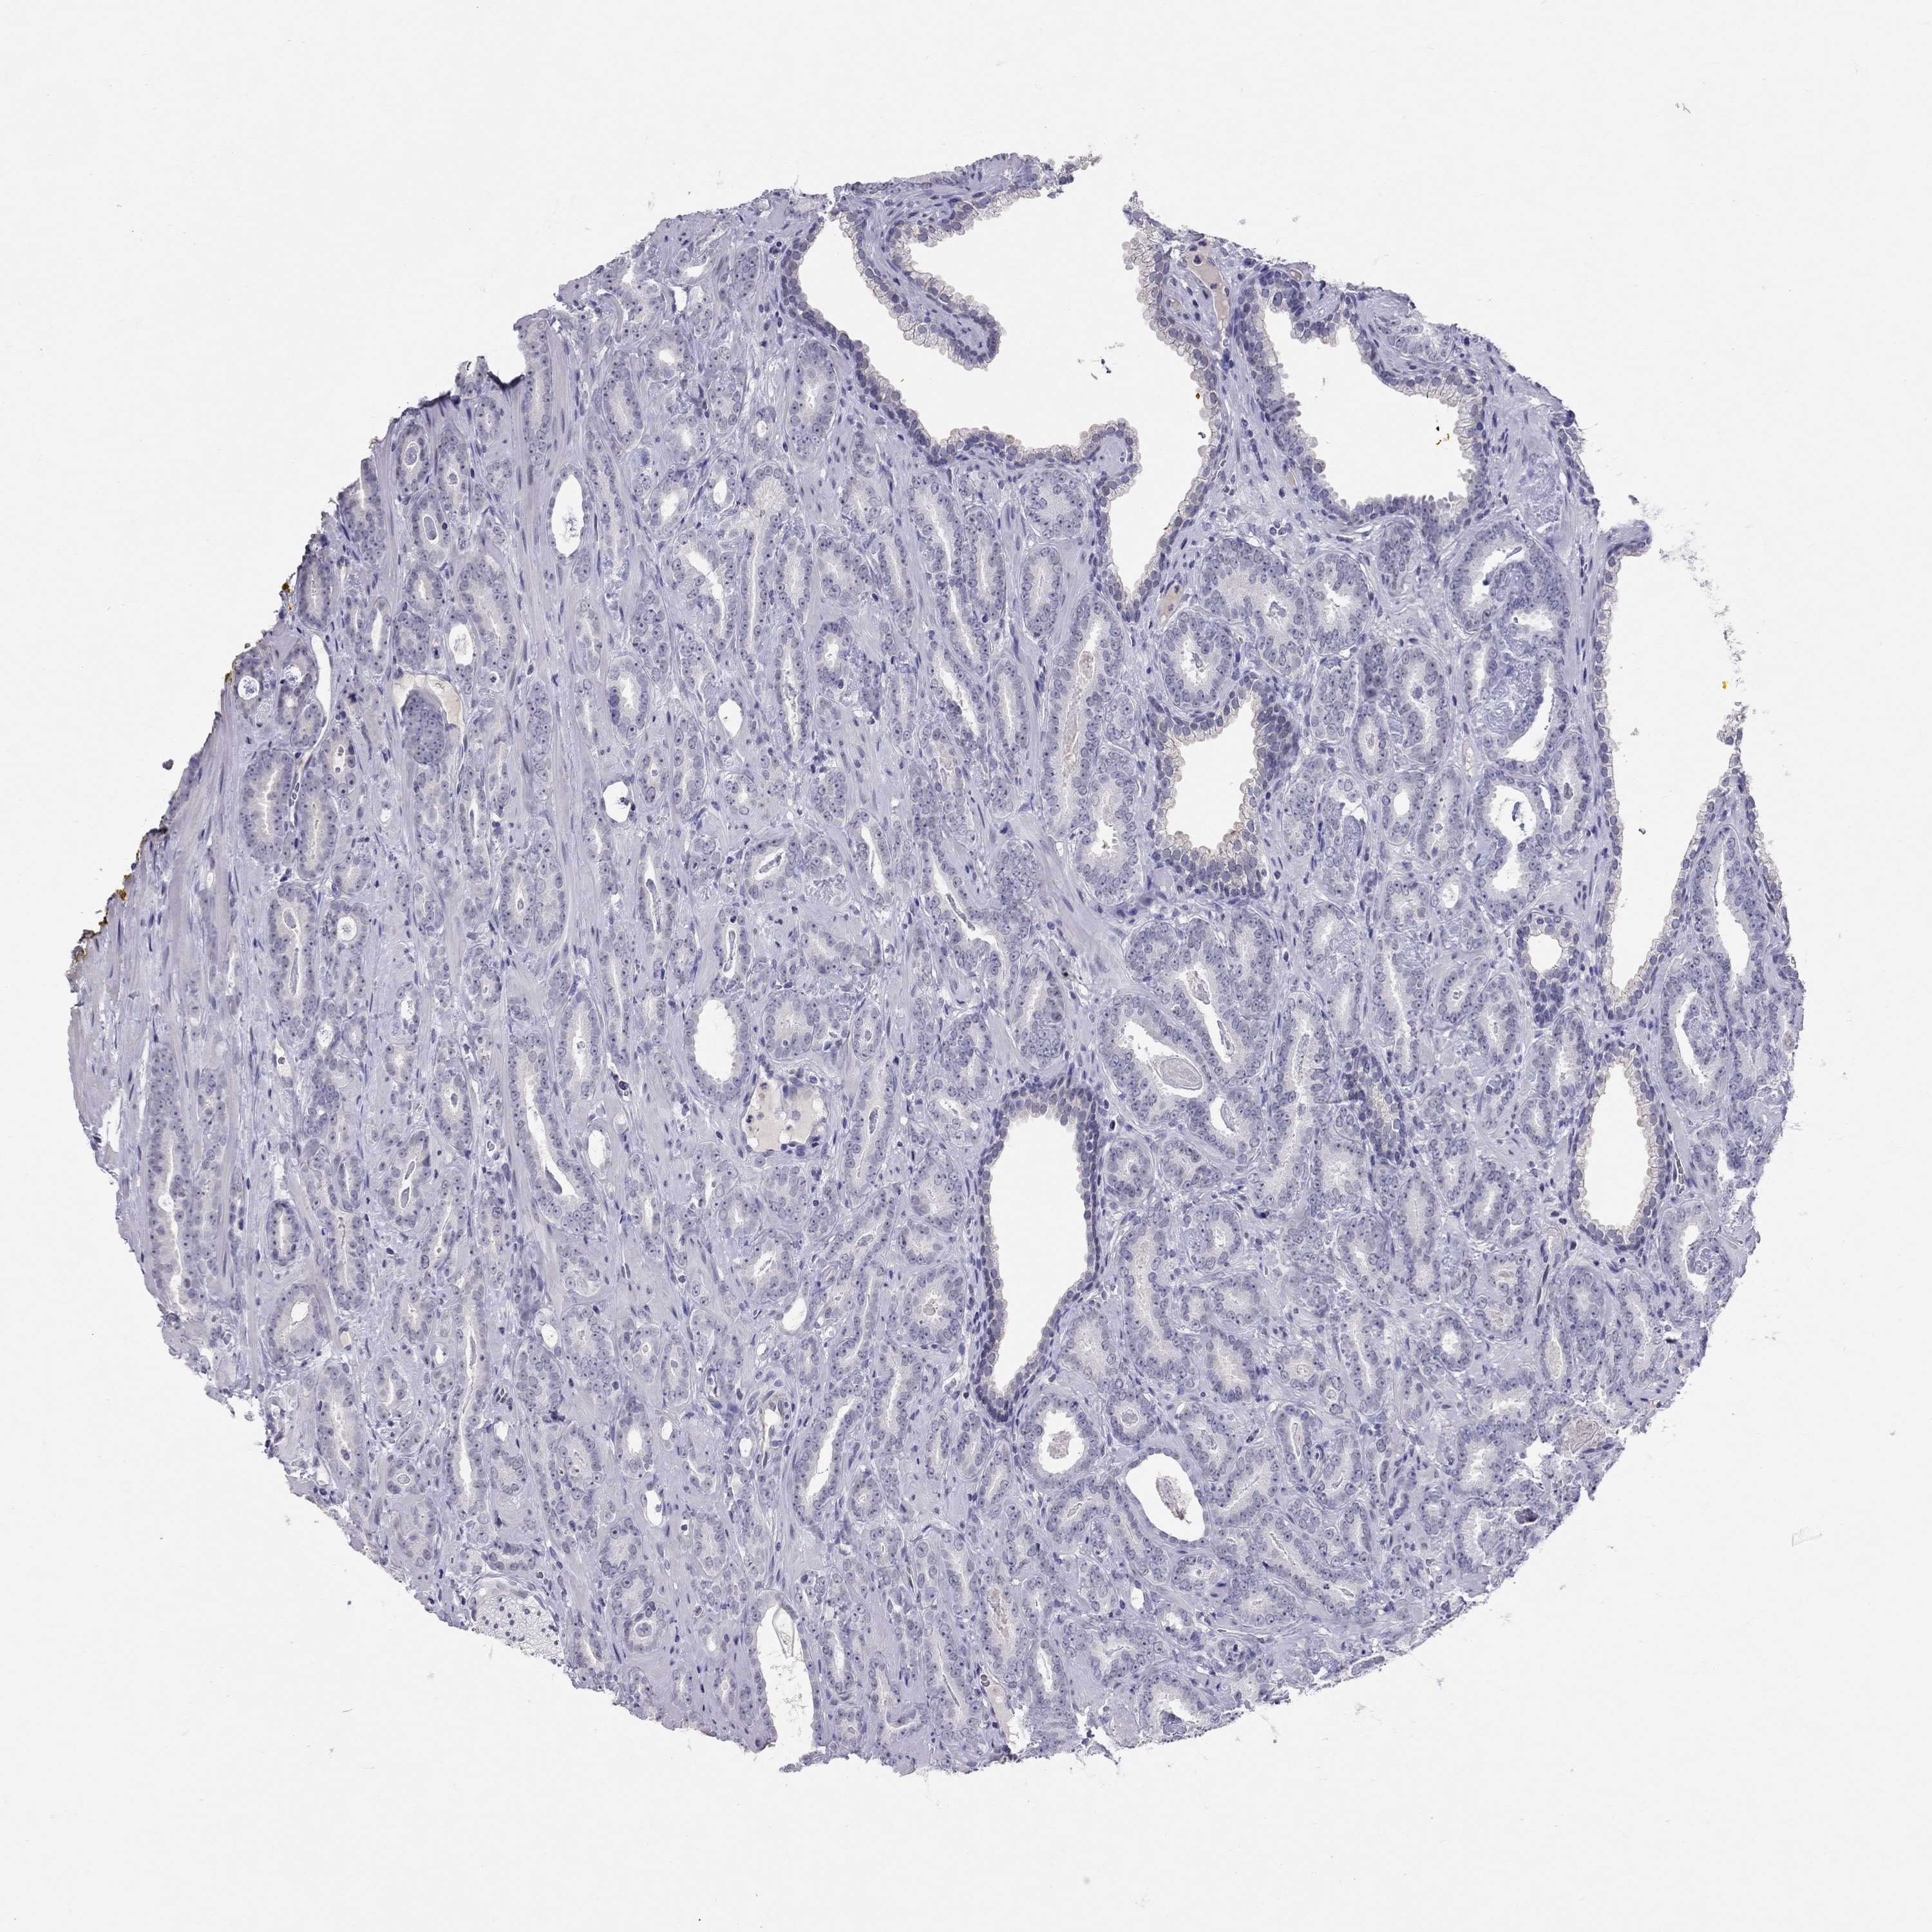

PROSTATE CANCER - Protein expressioni

A mouse-over function shows sample information and annotation data. Click on an image to view it in a full screen mode. Samples can be filtered based on level of antibody staining by selecting one or several of the following categories: high, medium, low and not detected. The assay and annotation is described here.

Note that samples used for immunohistochemistry by the Human Protein Atlas do not correspond to samples in the TCGA dataset.

Antibody stainingi

Antibody staining in the annotated cell types in the current human tissue is reported as not detected, low, medium, or high, based on conventional immunohistochemistry profiling in selected tissues. This score is based on the combination of the staining intensity and fraction of stained cells.

Each image is clickable and will lead to virtual microscopy that enables deeper exploration of all samples and also displays staining intensity scores, fraction scores and subcellular localization as well as patient and tissue information for each sample.

Antibody HPA077658

Antibody HPA077748

Staining

High

Medium

Low

Not detected

Intensity

Strong

Moderate

Weak

Negative

Quantity

>75%

75%-25%

<25%

None

Location

Nuclear

Cytoplasmic/membranous

Cytoplasmic/membranous,nuclear

Adenocarcinoma, Medium grade

Adenocarcinoma, High grade

Adenocarcinoma, NOS

Adenocarcinoma, Low grade